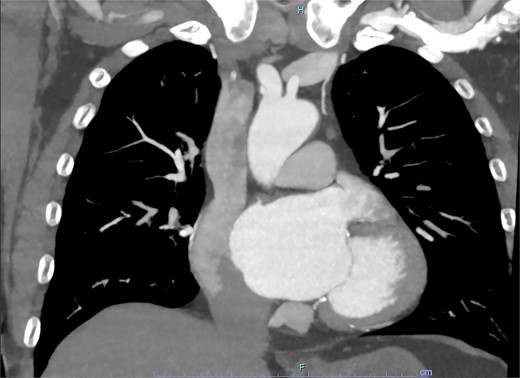

On arrive to the emergency department, the patient was found to be hypertensive with a blood pressure of 220/120 mmHg. Physical examination of the patient revealed no significant clinical findings. Serial troponins with corresponding ECG’s were undertaken which demonstrated no new evidence of myocardial ischaemia. Based upon the patient’s symptomatology, he underwent a CT aortogram which demonstrated a dissection arising from the proximal brachiocephalic artery. No dissection was noted in the ascending aorta, and there was no evidence of the brachiocephalic artery dissection extending into the subclavian or carotid arteries (Figs 1–3).

Axial slice from CT aortogram demonstrating the proximal aspect of the dissection flap.